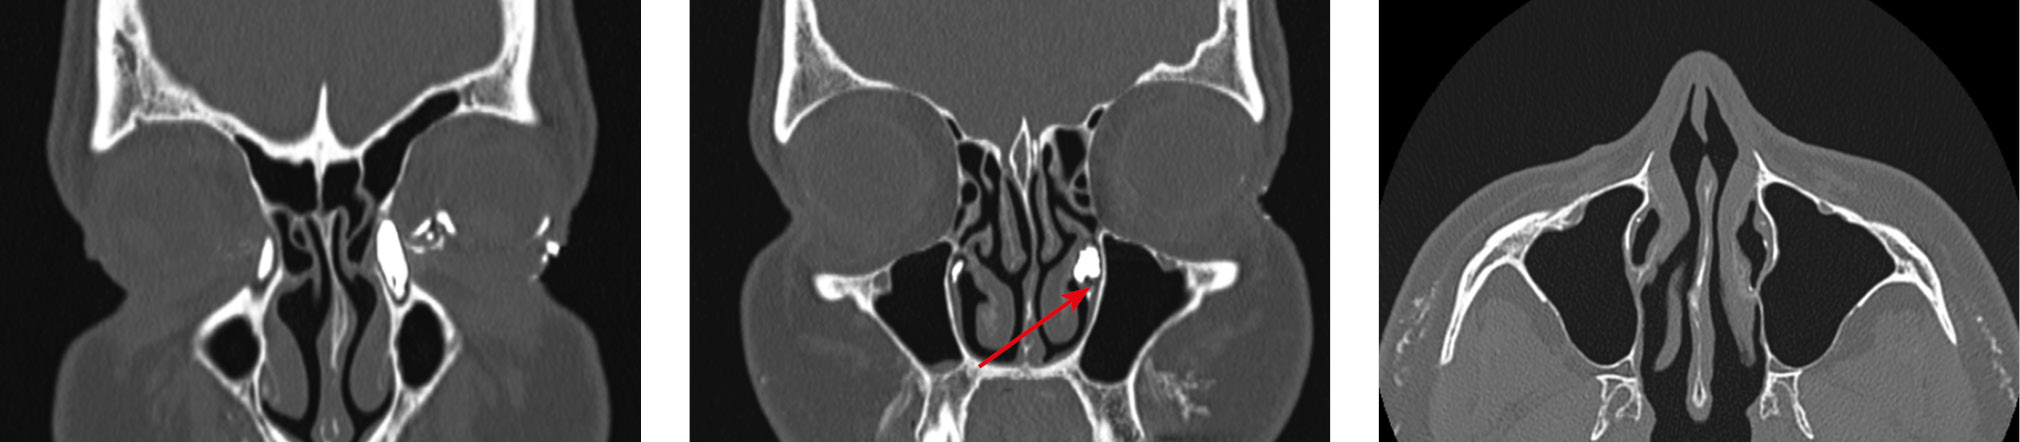

В одном из случаев непроходимость СОП возникла после эндоназальной гайморотомии, выполненной прелакримальным доступом (рис. 7). Этот доступ был предложен N. Liang и соавт. в 2008 г. в качестве альтернативы доступу через переднюю стенку ВЧП [20]. По рекомендациям авторов, с целью избежания возможных осложнений при планировании такой операции необходимо предварительно оценить расстояние от заднего края передней стенки ВЧП до переднего края НСК по данным МСКТ, а также размеры самого прелакримального кармана [20–22]. По мнению H.B. Koo и соавт. [22], в ситуациях, когда это расстояние недостаточно (менее 3 мм — 1-й тип либо находится в диапазоне от 3 до 7 мм — 2-й тип строения), следует отдать предпочтение другим видам доступов.

Рис. 7. Нарушение проходимости (дакриостеноз) носослезного протока на уровне нижней трети (OU) после гайморотомии прелакримальным доступом. Справа контрастное вещество, введенное в слезоотводящие пути, частично дренируется в верхнечелюстную пазуху

Fig. 7. Obstruction (dacryostenosis) of the lacrimal ducts at the level of the lower third (OU) after maxillary sinusotomy using the prelacrimal approach. Right maxillary sinus partial drainage of contrast injected into the lacrimal ducts